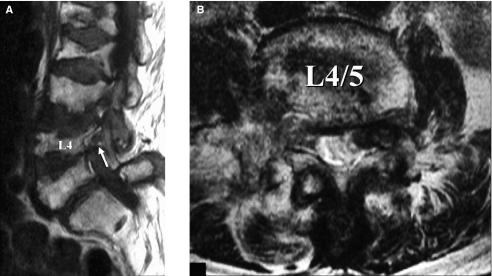

The affected nerve roots were L4 in four patients and L3 in two patients. Foraminal stenosis was not demonstrated in magnetic resonance images in four of the six patients. Selective radiculography with nerve root block reproduced pain, manifested blocking effect, and demonstrated compression of the nerve root by the superior articular process of the lower vertebra in all patients. Conservative treatment was performed on one patient, and surgery was conducted for the rest of the five patients; radiculopathy was improved in all patients.

结果

4 例患者的受累神经根为 L4,2 例患者为 L3。6 例患者中,有 4 例磁共振成像未显示椎间孔狭窄。选择性神经根造影结合神经根阻滞可重现疼痛,表现出阻滞效应,并显示下位椎体上关节突对神经根的压迫,所有患者均如此。对 1 例患者进行保守治疗,其余 5 例患者进行手术治疗;所有患者的神经根病均得到改善。